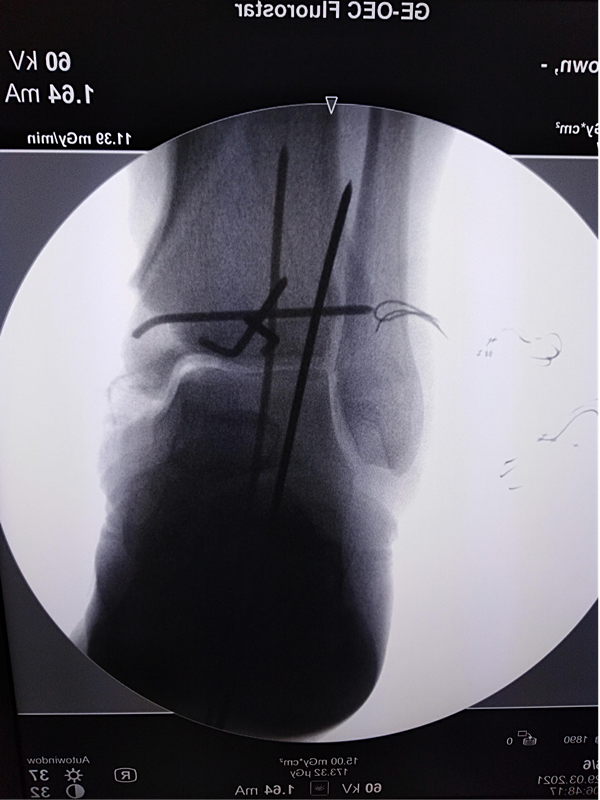

第一次手术拍片